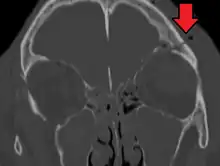

Basilar skull fracture

A basilar skull fracture is a break of a bone in the base of the skull.[1] Symptoms may include bruising behind the ears, bruising around the eyes, or blood behind the ear drum.[1] A cerebrospinal fluid (CSF) leak occurs in about 20% of cases and may result in fluid leaking from the nose or ear.[1] Meningitis occurs in about 14% of cases.[2] Other complications include injuries to the cranial nerves or blood vessels.[1]

A basilar skull fracture typically requires a significant degree of trauma to occur.[1] It is defined as a fracture of one or more of the temporal, occipital, sphenoid, frontal or ethmoid bone.[1] Basilar skull fractures are divided into anterior fossa, middle fossa and posterior fossa fractures.[1] Facial fractures often also occur.[1] Diagnosis is typically by CT scan.[1]